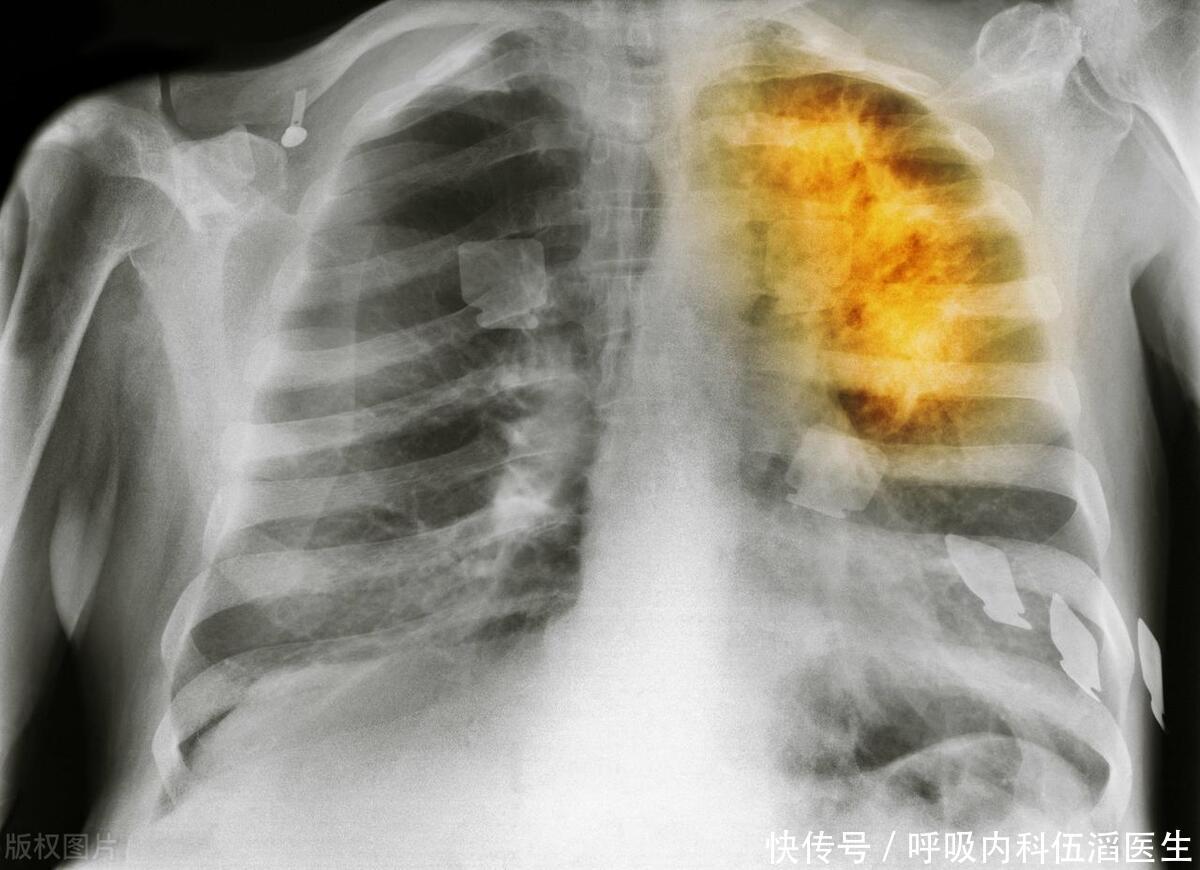

肺癌,作为全球最为常见的癌症之一,其高死亡率备受关注。其严峻形势迫切需要引起社会各界的高度重视和关注。肺癌往往在早期无明显症状,导致晚期诊断增加了治疗的挑战和风险。这强调了早期筛查的必要性,以便及早发现和治疗该疾病。然而,身体往往会通过各种迹象向我们发出健康警报,其中一些迹象甚至可能在不太显眼的地方出现,比如双腿。本文将探讨肺癌与双腿出现的三个可能迹象,以及为什么早期筛查对于提高生存率至关重要。

肺癌早期发现关系到治疗成功率和生存率,这一现实不容小觑,应引起社会广泛关注和高度重视。早期肺癌通常可以通过手术完全切除,而晚期肺癌的治疗选择则更加有限,通常涉及化疗、放疗或靶向治疗等方法。

早期筛查采用低剂量计算机断层扫描(LDCT),这种专为尽早发现肺癌而设计的影像学检查备受肯定,其精准度和有效性在专业领域获得了广泛认可。据已有证据表明,定期进行低剂量计算机断层扫描(LDCT)筛查已被证实对于长期吸烟等高风险人群可显著降低肺癌死亡率。